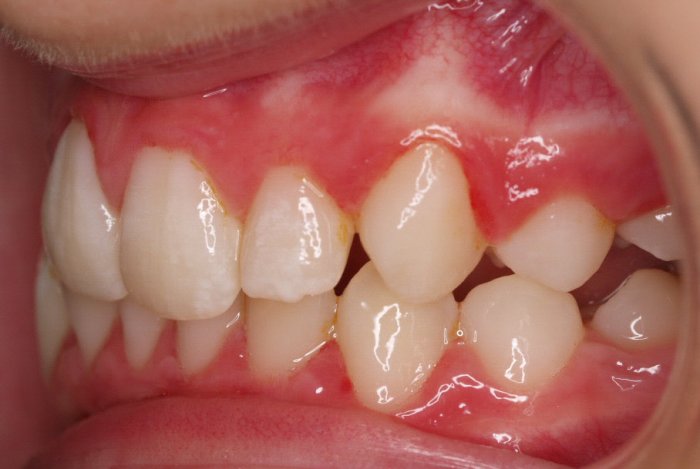

El paciente A.J. de 11 años, acude a nuestra consulta con apiñamiento maxilar importante. El canino lateral (12) está en mordida cruzada. Presenta una Clase II molar y canina, y la línea media está desviada. Se realizó un tratamiento con brackets autoligables metálicos de smartclip 022. La duración del tratamiento fue de 22 meses.